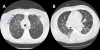

Sickle cell disease (SCD) is a common monogenetic disorder with high associated morbidity and mortality. The pulmonary complications of SCD are of particular importance, as acute chest syndrome and pulmonary hypertension have the highest associated mortality rates within this population. This article reviews the pathophysiology, diagnosis, and treatment of clinically significant pulmonary manifestations of SCD, including acute chest syndrome, asthma, and pulmonary hypertension in adult and pediatric patients. Clinicians should be vigilant in screening and treating such comorbidities to improve patient outcomes.